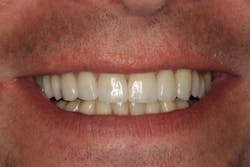

Through working with Darren, we were able to provide the necessary treatment to obtain the five requirements of occlusal stability. He now has stable stops on all teeth, anterior guidance in harmony with the envelope of function, anterior teeth that provide immediate posterior disclusion in protrusive, and he no longer has working and balancing side excursive interferences.

Overall, the case closely followed our treatment plan blueprint because of proper diagnosis and planning. Darren was comfortable with his envelope of function, occlusal stability was restored, and he was thrilled with his natural, esthetically pleasing smile.